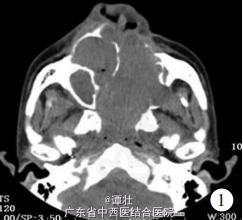

男, 56 岁。 因左侧鼻翼良性肿物切除术后 10年,左侧面部凸出肿物 3 年余,肿瘤表面间断出血 1个月入院。 10 余年前曾出现左侧鼻塞、左侧鼻翼肿物,于外院行手术治疗, 术后病理结果回报为良性 ,术后面部形态正常。 3 年前再次出现左侧鼻塞,左侧鼻翼凸出黄豆大小肿物,外院行CT(如图)。此后左侧面部肿物逐渐增大,覆盖眼球、嘴唇,遮挡视野并妨碍进食。 1 个月前面部肿物表面开始间断出血,每次出血量约 100 ml,可自行停止。 右眼幼时失明,原因不明。